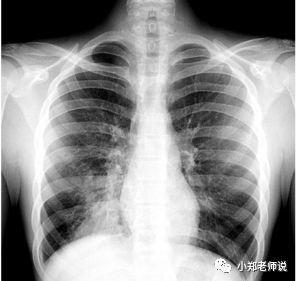

和其他肺炎一样,拍胸片也是重要的检查方法

不过胸片并不能可靠区分支原体肺炎,和其他肺炎